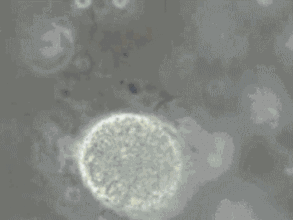

精液射出后立即形成典型的半透明凝胶状,室温下在数分钟内,精液开始液化(变稀),最后变成均匀的水样物,只看到很小的凝块。

室温下精液一般在15分钟内通常都能完全液化,很少超过60分钟。如果液化时间超过60分钟,有可能存在精液不液化的问题,需要到医院就诊。

这里要说一个小知识点,很多小伙伴都在问,他朋友的精液中有一些小颗粒,像果冻一样,这是有什么问题吗?其实,正常的精液可以含有不液化的胶冻状颗粒,不过不用担心,它们没有什么临床意义,也不代表你有什么问题。